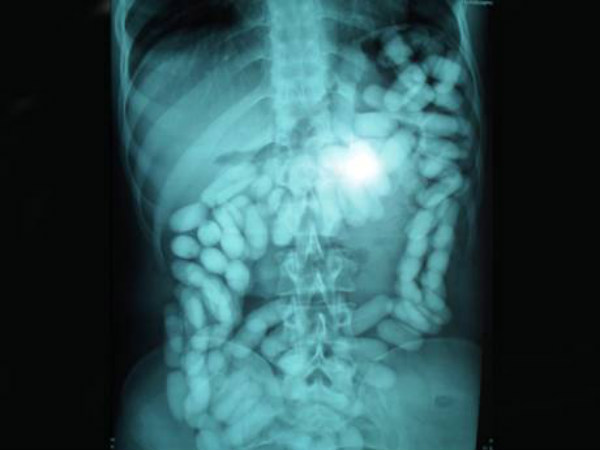

Drugs

A Nigerian man was caught at an airport in Malaysia while he was trying to export 52 capsules of methamphetamine. Wonder how would he get all these capsules out of his body! Phew.